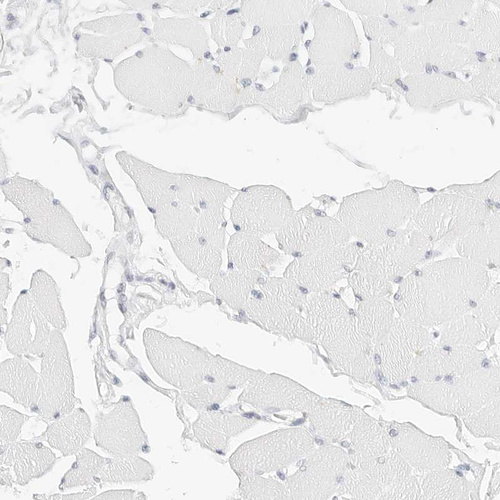

Immunohistochemistry analysis in human spleen and skeletal muscle tissues using HPA024353 antibody. Corresponding CD22 RNA-seq data are presented for the same tissues.